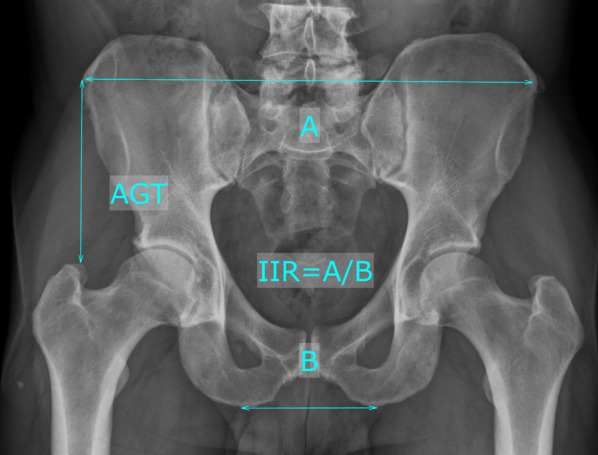

Methods: A retrospective, single-center, multi-surgeon, comparative propensity-score matched study of a cohort of 1826 short stem THAs was conducted. A total of 39 PFFs within the first 90 days after surgery was matched on a 2:1 ratio to non-fracture patients. The morphology of the proximal femur was analyzed with canal flare index (CFI), canal-calcar ratio (CCR), canal-bone ratio (CBR), morphological cortical index (MCI), and femoral cortical index (CI). The pelvic morphology was analyzed with ilium-ischial ratio (IR), distance anterior superior iliac spine to the tip of the greater trochanter (AGT). Both groups were analyzed regarding several parameters for femoral and pelvic morphology in non-parametric testing and univariate regression analysis.

Results: A significantly higher AGT was detected in the fracture group (104.5 mm ± 18 versus 97.4 mm ± 9.8; p = 0.016). All other femoral and pelvic parameters did not differ between both groups, also when compared depending on the Vancouver type of the PFF.